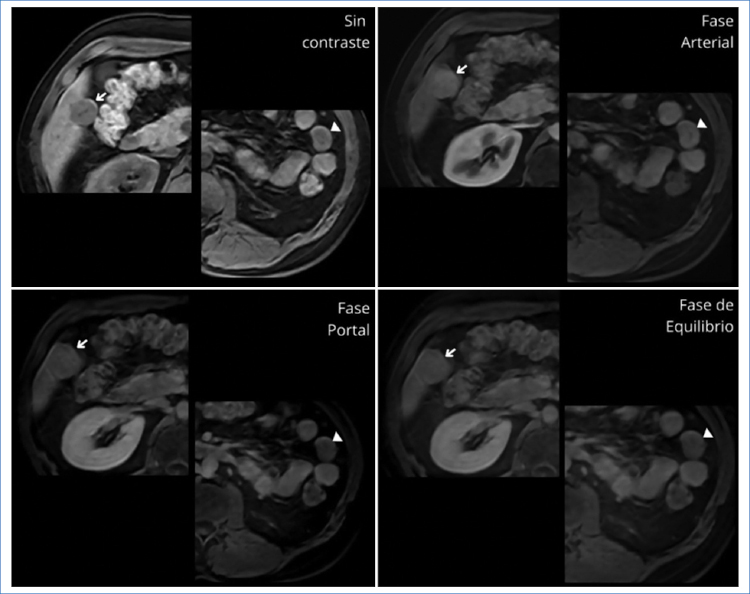

Se decide realizar una resonancia magnética (RM) para mejor caracterización de dichas lesiones, las cuales, junto con las observadas a nivel peritoneal ya descritas anteriormente como esplénulos por su estabilidad en el tiempo, son hipointensas en las secuencias ponderadas en T1, ligeramente hiperintensas en T2 y FATSAT, con tenue restricción de la difusión (DWI) y con similar realce tras la administración del contraste paramagnético (Figs. 2a4).

En los estudios de TC multidetector y RM, el tejido esplénico heterotópico tiene la misma apariencia e igual comportamiento que el bazo tras la administración del contraste endovenoso. En la TC sin contraste, la lesión es isodensa con respecto al parénquima hepático y presenta realce en fase arterial, difícil de diferenciar de un adenoma o un hepatocarcinoma4. En la RM, previo a la administración de contraste paramagnético, la lesión es homogéneamente hipointensa en las secuencias ponderadas en T1 e hiperintensas en las ponderadas en T2; después de la administración del gadolinio es hiperintensa en comparación con el resto del parénquima hepático1,5.

El hepatocarcinoma también se propone como uno de los diagnósticos diferenciales4. Sin embargo, este suele estar asociado a hepatopatía crónica como antecedente principal y el patrón característico es de realce en fase arterial, con lavado en fases portal/tardía, dando apariencia de cápsula periférica en estas últimas6. Los adenomas hepatocelulares, otro diagnóstico planteado, son tumores encapsulados grandes y bien delimitados, cuyo patrón radiológico muestra una lesión con realce homogéneo en la fase arterial tardía, que permanecerá isodensa al hígado en fases posteriores.